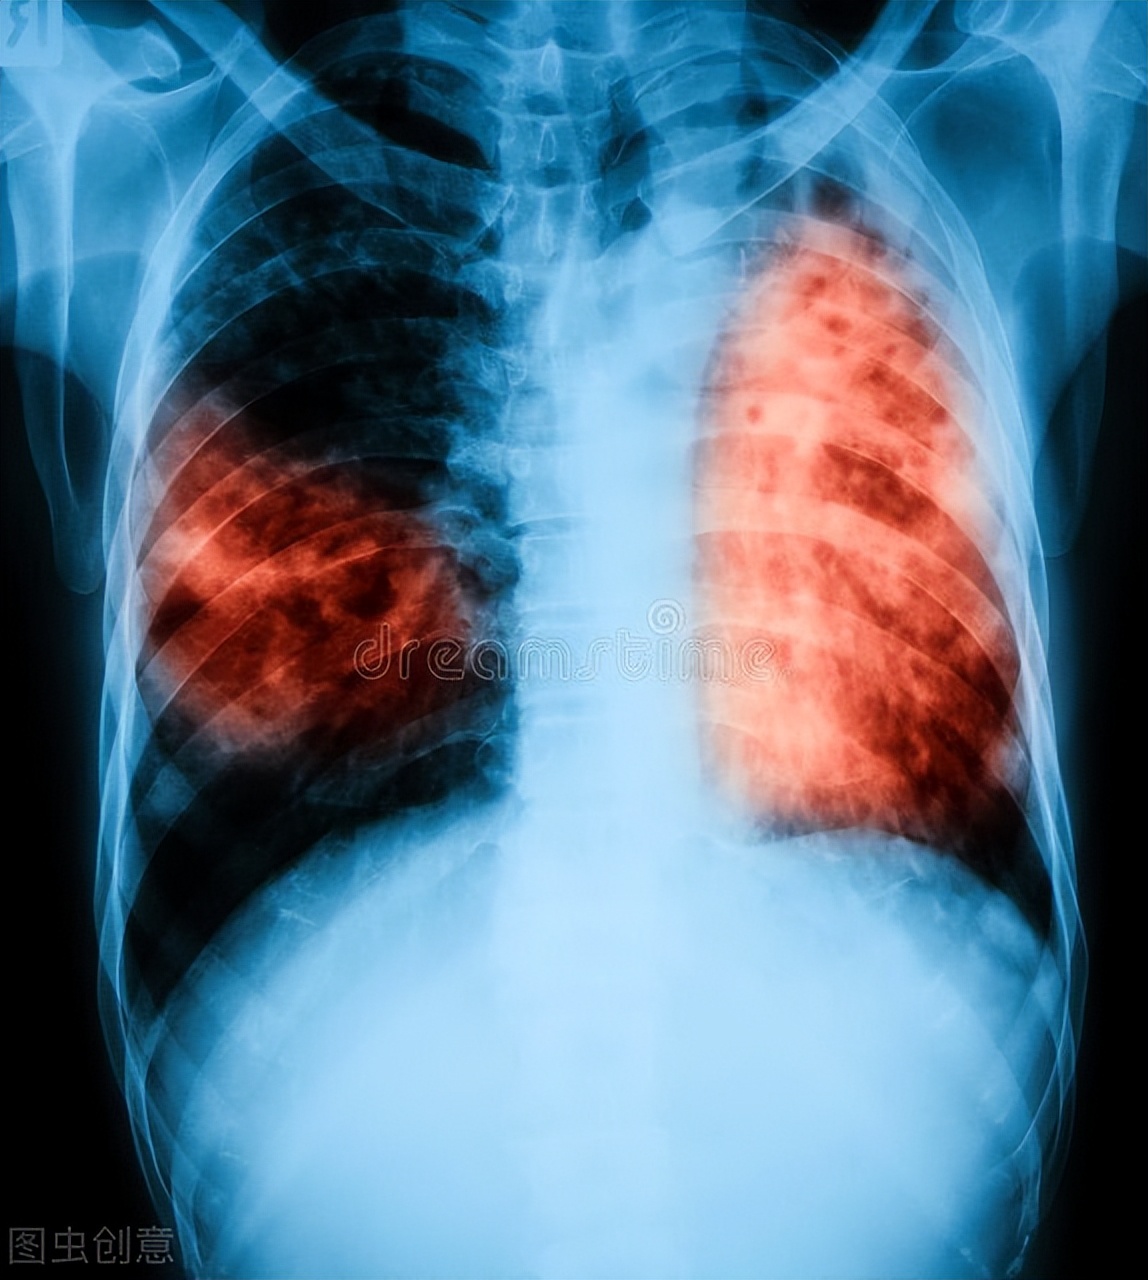

淋巴结结核多是因为肺结核或身体其他部位结核继发而来,如果患者有肺结核或其他部位结核病史,就能高度怀疑。